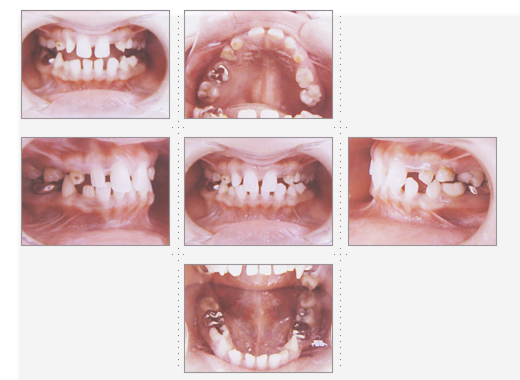

症例3

23才 女性

沖縄のリゾートホテルへ就職が内定している為、通院できるのは4ヶ月という条件で来院。

すべて、3ヶ月で完成し、出発されました。明るい笑顔で接客されていることと思います。